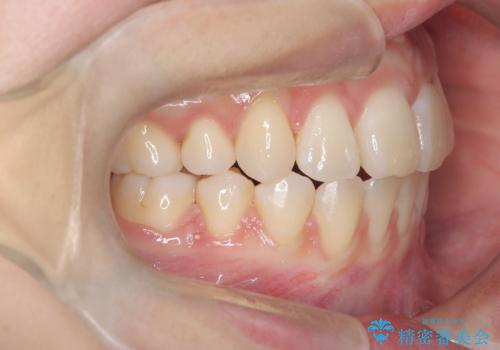

ハーフリンガル矯正|下顎前歯3本の特異症例を抜歯矯正で改善

- 患者様は下顎の前歯が3本しかないという特異な歯列を持ち、噛み合わせのバランスが崩れていました。上下の歯の本数が通常と異なるため、抜歯部位の選定が重要となるケースでした。診査の結果、歯の位置や咬合のバランスを考慮し、上顎の両側小臼歯2本と左下の小臼歯1本を抜歯することで、上下の噛み合わせを整える方針としました。矯正装置は、**目立ちにくいハーフリンガル(上顎は裏側矯正・下顎は表側矯正)**を採用しました。

まず、計画通りに抜歯を行い、歯列のスペースを確保しました。上顎は裏側矯正(リンガル)で目立たないように配慮しながら歯を後方へ移動し、下顎は表側矯正を使用して、3本の前歯の位置関係を調整。上下の歯の噛み合わせを細かくコントロールしながら、全体のバランスを整えました。治療後は「歯並びがきれいになり、噛み合わせもしっかり合うようになった」と患者様にも満足していただけました。